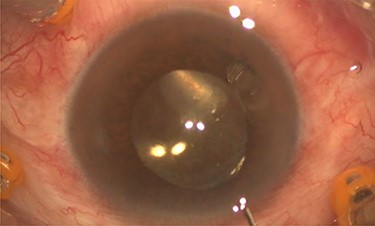

On examination, both eyes showed a quiet conjunctiva with clear corneas and quiet pseudophakia. Anterior chamber was deep and equal in both eyes. Left eye showed dense turbid fluid behind the IOL, with multiple pitting on the IOL, indicating a previous trial of Nd:YAG capsulotomy (Fig. 1). Posterior capsule could not be visualized by the slit lamp. Right eye showed a clear capsular bag with a good view of the fundus. Fundus exam showed mild non-proliferative diabetic retinopathy and dry macula in the right eye and no view of the fundus in the left eye.

Pre-operative slit lamp photo showed turbid fluid behind the IOL, and the IOL pitting indicates a previous trial of YAG capsulotomy.